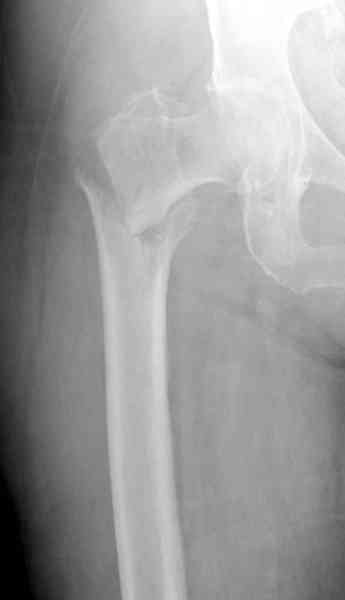

Александр, поздравляю от души, отличная работа, вообще-то и у меня тоже были опасения по поводу латеральной стенки. Идеальное показаниt к применению импланта закрытым методом при таких переломах, когда болт замыкается в штифте, конструкции придается угловая жесткость, примерно как в Blade Plate.

Здесь сканнированные снимки импланта и операционные снимки больной.

Уважаемые коллеги, Александр Николаевич!!! Очень достойный выход из сложнейшей ситуации. У нас лежит похожий пациент. Хотелось бы обсудить вот какой ворос. Почти все ятрогенные переломы шейки бедра при антеградной штифтовании - вертикальные. Понятно, что при многоуровневых переломых не до жиру. Но все же, как фиксировать вертикальный перелом шейки? Только отрепонировав или вальгировать проксимальный отдел бедра(если есть такая техническая возможность)???